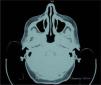

Realizamos una biopsia del cuero cabelludo de las áreas afectadas. La muestra reveló un aumento en el grosor del TCS debido a una hiperplasia del mismo que incluso se extendía hacia la dermis. Además, se apreciaba edema dérmico y un leve infiltrado linfocítico perivascular en la dermis superficial (fig. 2). No existía depósito de mucina en la dermis o en el tejido subcutáneo (azul alcián negativo). La epidermis era normal, al igual que los folículos pilosos. Una tomografía computarizada (TC) puso de manifiesto un engrosamiento difuso del tejido subcutáneo en el vértex y áreas occipitales que medía 1,52cm (fig. 3).